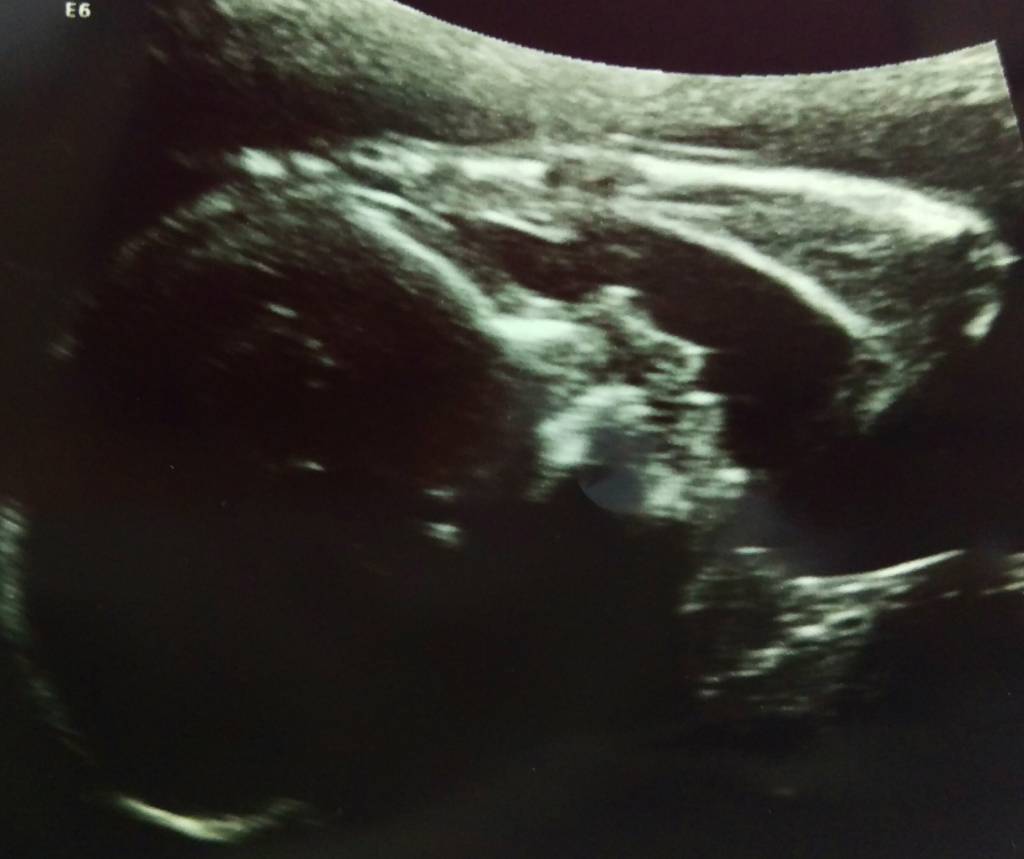

Młoda czkawkuje z regularną przyjemnością od dawna, główkę ma od miesięcy po lewej stronie spojenia i od początku rytmicznie uderza podczas czkawki tylko w tym miejscu. Czasem czuję te jakby wzdrygnięcia, choć nie wiem, jak to określić, bo to niekoniecznie takie uczucie jednak. No i ukochała sobie prawą stronę na wypychanie kończyn - mimo to, choćbym nie wiem, jak na te ataki marudziła, to lubię, gdy tak wystrzeli czasem jak z procy, bo kiedy głaszczę w danej chwili brzuch w takim miejscu, jestem w stanie wyczuć różne nieregularne kształty. Szkoda tylko, że nie wiem, czego dotykam, ale jest ewidentnie elementem boksującym mojej panny.